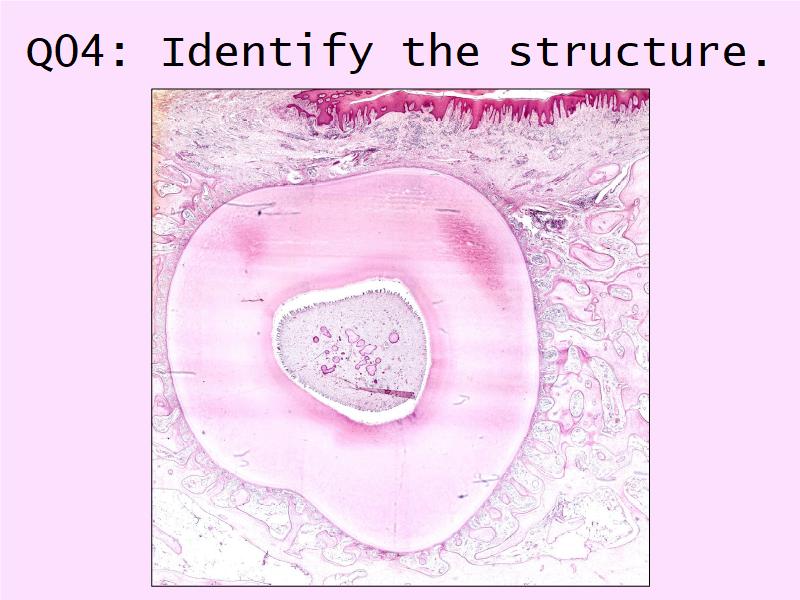

Q01: Terminology

On the next slide, a set of 16 terms will be listed. For each term, mark YES if you know or recognise the term, NO if you don't know the term.Yes = I know or recognise the term

No = I have no idea at all

Q01: Yes or No

|

1. Lumen 2. Low Density Lipoprotein 3. Endothelium 4. Intima 5. Extracellular matrix 6. Monocyte 7. Macrophage 8. Apoptosis |

9. Necrosis 10. Hypertension 11. Arterial wall 12. Smoking 13. Diabetes 14. Smooth muscle cell 15. Plaque 16. Thrombus |

Q01: Yes or No

|

1. Lumen 2. Low Density Lipoprotein 3. Endothelium 4. Intima 5. Extracellular matrix 6. Monocyte 7. Macrophage 8. Apoptosis |

9. Necrosis 10. Hypertension 11. Arterial wall 12. Smoking 13. Diabetes 14. Smooth muscle cell 15. Plaque 16. Thrombus |

9 of 16 = histology

7 of 16 = commonly occuring